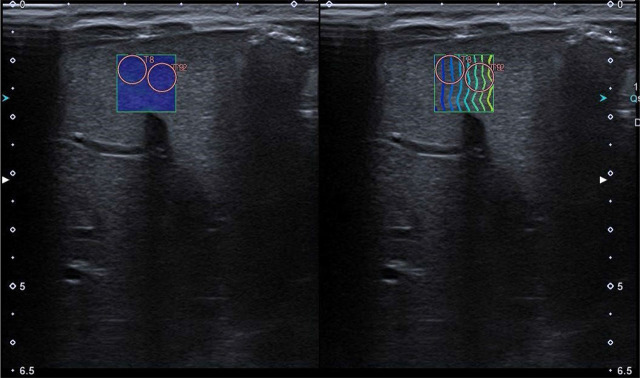

Materials and methods: We performed two-dimensional shear wave elastography of the liver, spleen and kidneys using a linear transducer at least 60 minutes after food intake in a group of 58 healthy, full-term, spontaneously breathing newborns. A series of 5 measurements using 5-mm-diameter regions of interest were performed, with the results expressed in m/s and kPa. Exam feasibility was assessed using the IQR/Median ratio as ≤30% for kPa, and ≤15% for m/s. Descriptive statistics, Shapiro-Wilk W, Levene's, Mann-Whitney U tests and Spearman correlation analysis were used for statistical assessment.

Abstract Image